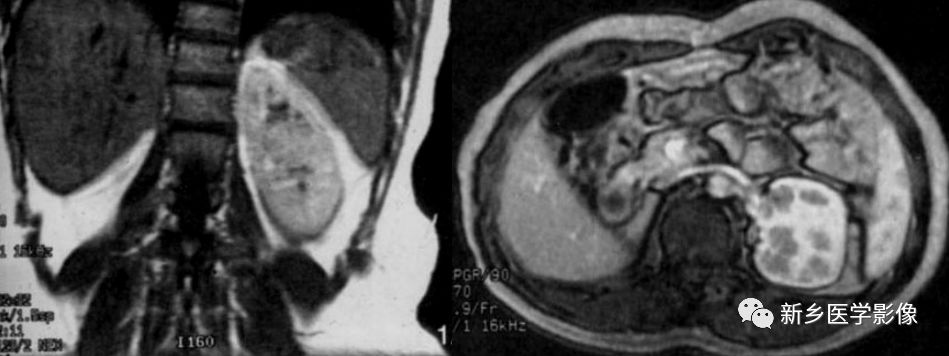

MR特点

双肾下极越过中线,以实质或纤维性连接。合并结石、积水可见不规则T1WI低、T2WI低或高信号,边缘清晰及扩大的肾盂。合并肿瘤可见不规则的T1WI低、T2WI低、高信号,合并出血或坏死可出现 明显T1WI低、T2WI低信号或高信号。冠状面可见拉长的下肾盏结构,可见到起源于主动脉较低水平的多支供血动脉及其他畸形。

讨论

马蹄肾是最常见的融合肾类型,不合并肾肿瘤或炎症等病变时,临床无症状。CT和MR可明确诊断。但需注意并发症的存在及血供情况。

鉴别诊断

马蹄肾主要与其他融合,如乙状肾、块状肾和L形肾等进行区别。合并肿瘤巨大时,有时有困难。